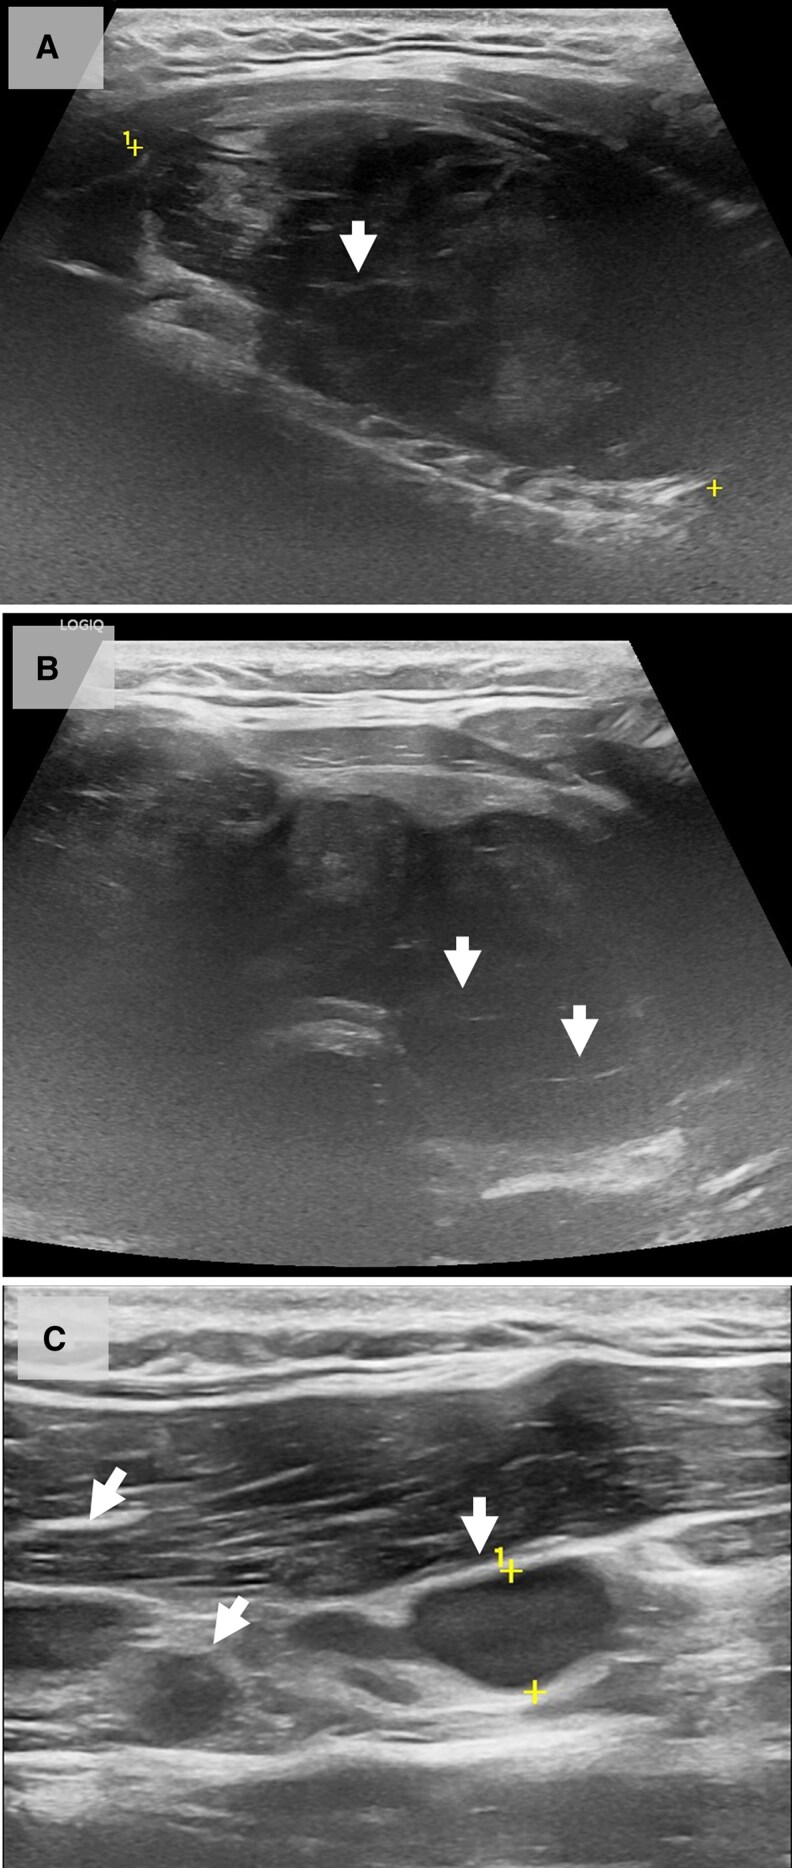

Primary thyroid lymphoma accounts for only 2% to 5% of all thyroid tumors, and Burkitt lymphoma of the thyroid is even rarer than other types of B-cell lymphoma. It is a highly aggressive non-Hodgkin lymphoma characterized by intermediate-sized lymphoid cells with a "starry sky" appearance and exhibits chromosomal translocations that activate the MYC oncogene. A male predominance and an aggressive clinical course with a high risk of central nervous system involvement and tumor lysis syndrome are all well-recognized features of Burkitt lymphoma. We present a case of a 28-year-old man with primary Burkitt lymphoma of the thyroid initially misdiagnosed as post-COVID thyroiditis. Core needle biopsy showed round, intermediate-sized lymphoid cells admixed with scattered tingible body macrophages displaying a "starry sky" appearance. Following the final histological diagnosis of primary thyroid Burkitt lymphoma, the patient received intensive chemotherapy. Six months after the diagnosis, the patient succumbed to disease progression, causing upper airway obstruction. Primary Burkitt lymphoma of the thyroid can cause pain and other symptoms due to the rapidly growing mass in the neck. Adequate pathological diagnosis with core needle biopsy rather than fine needle aspiration is essential for treatment planning and outcome improvement.